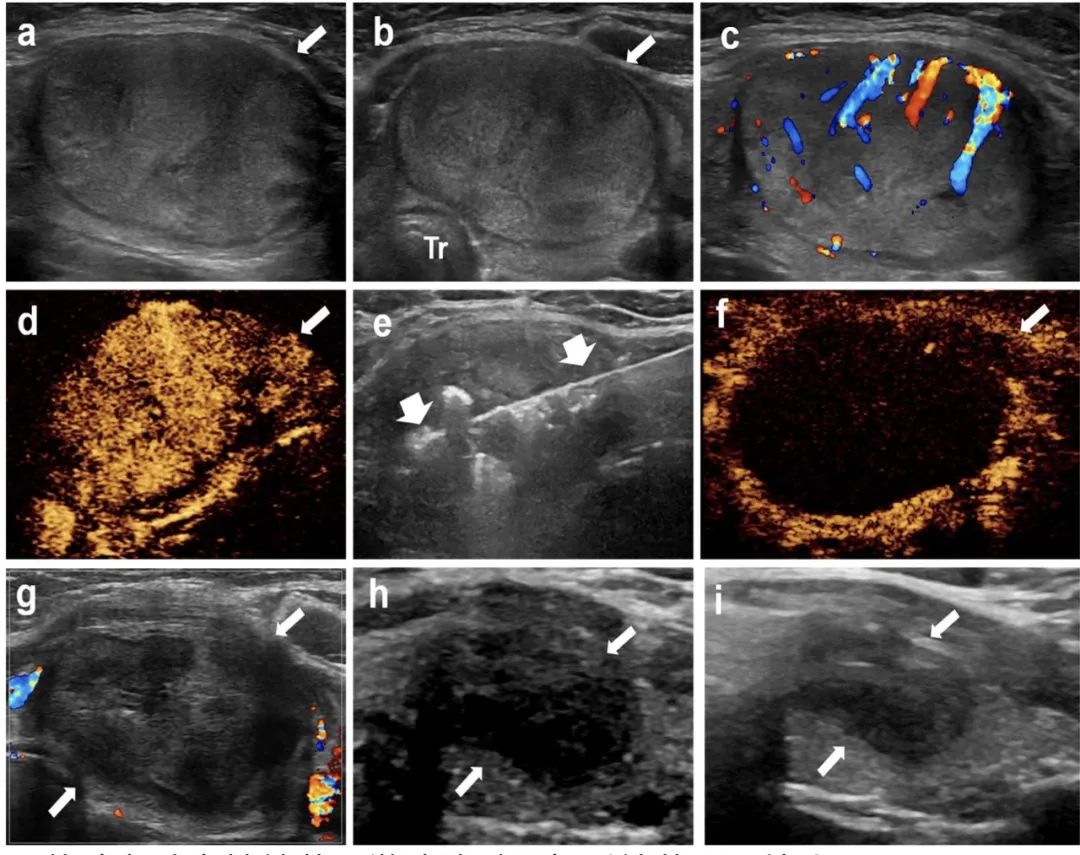

甲状腺左叶实性结节,微波消融4年后结节明显缩小